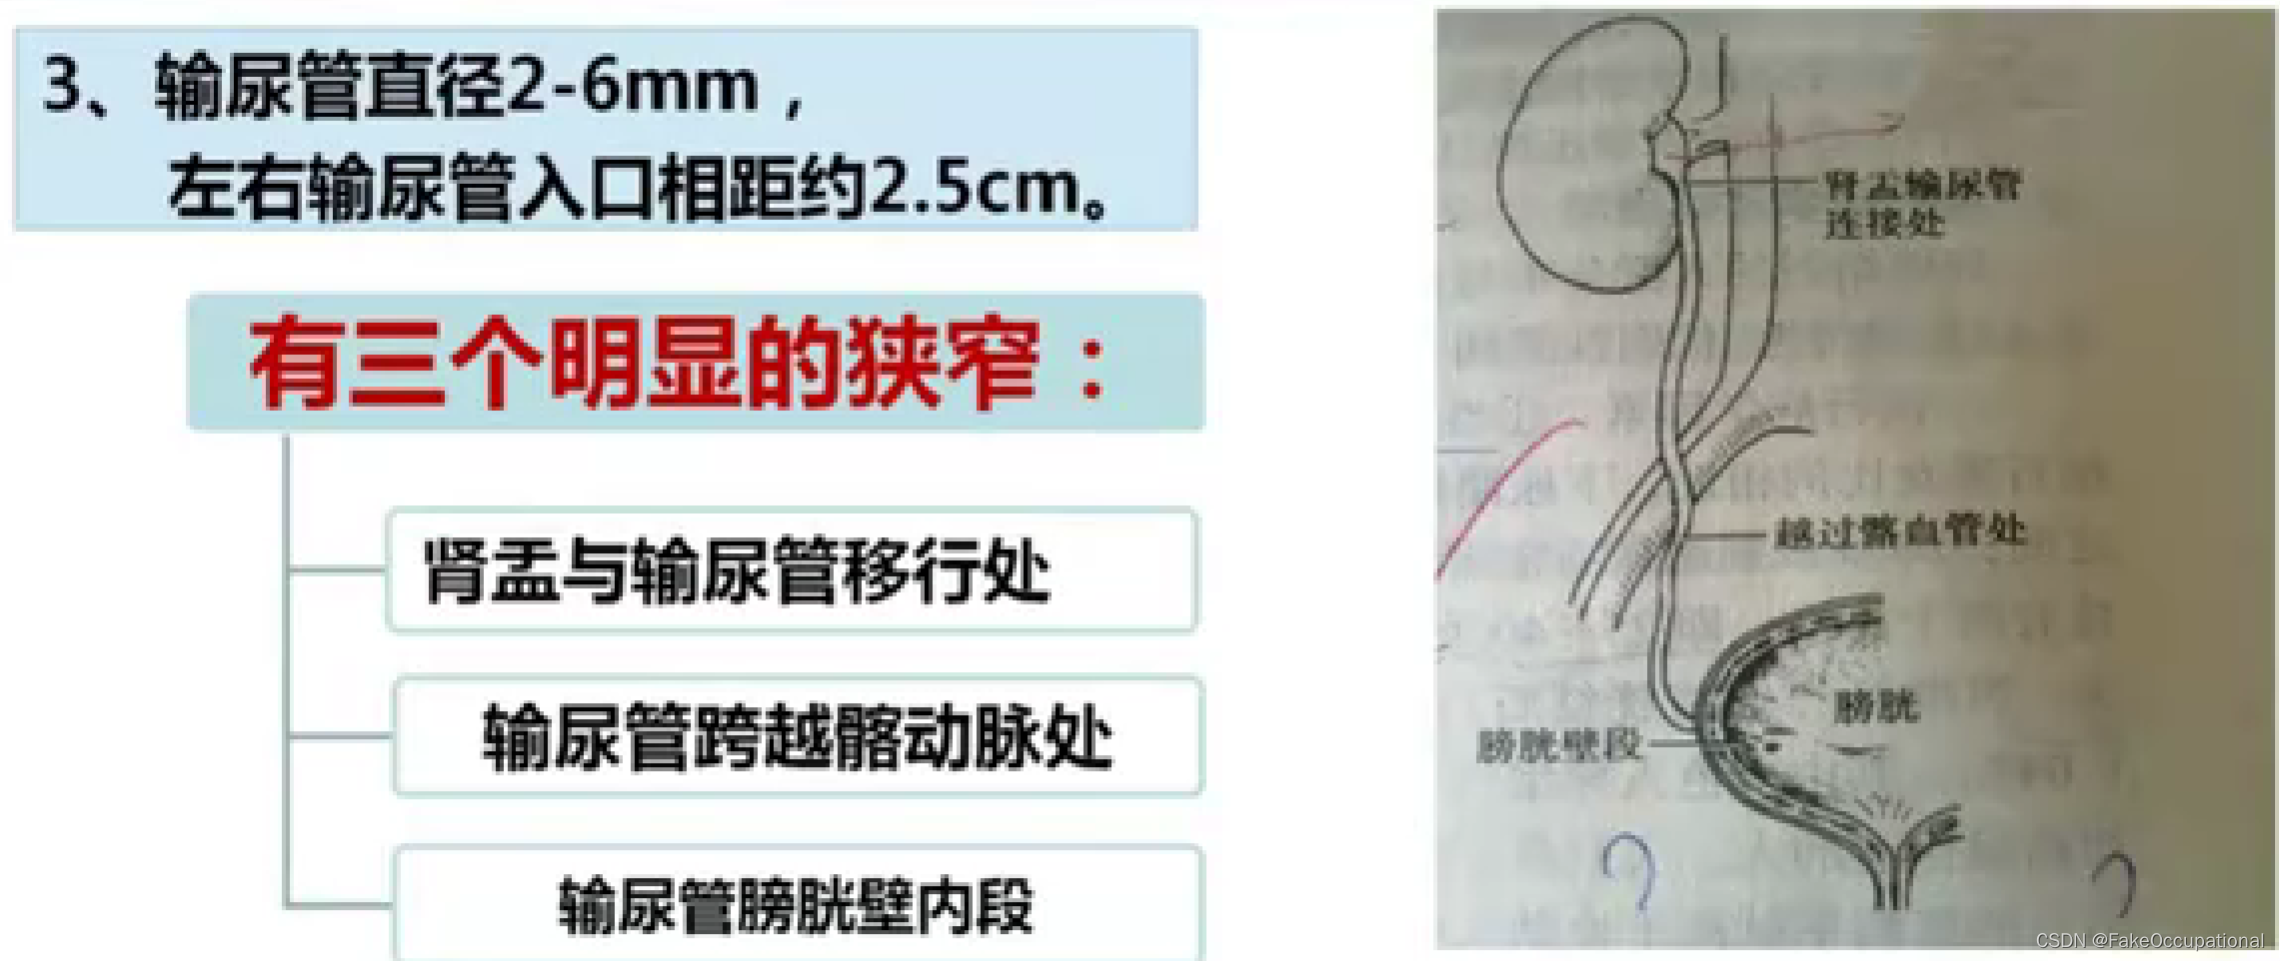

输尿管超声

- 1、回声较强的纤细管状结构,其内径不超过0.5cm,管壁光滑,清折,内为细条形无回声暗带

2、正常输尿管一般处于闭合状态下,一般不能显示。